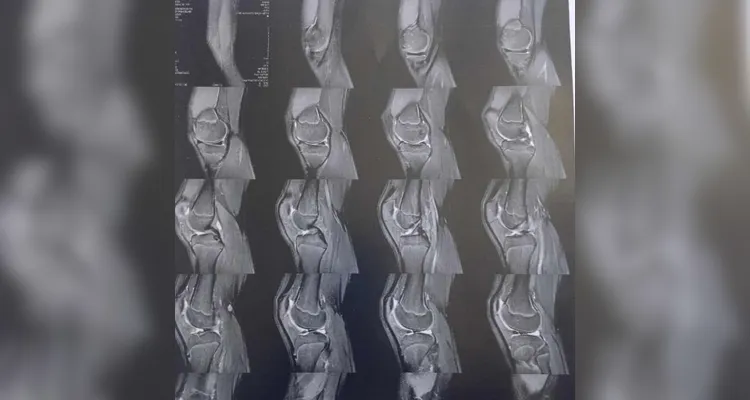

Confira abaixo a documentação contendo os exames e o custo da cirurgia.

A família do jovem Kaua Rodrigo Santos Gonçalves solicita a sua ajuda para a realização de uma cirurgia de caráter urgente que pode salvar a perna do jovem de 13 anos. No dia 14 de outubro, Kaua sofreu uma queda no colégio em que estuda em Ponta Grossa, o que resultou em uma fratura em seu joelho esquerdo. Com a lesão, o jovem passou a ter dificuldades de se locomover, necessitando de suporte dos familiares para locomoção diária.

Após a realização de exames, os médicos constataram a necessidade da realização de um procedimento cirúrgico com urgência. Kaua entrou na fila do Sistema Único de Saúde (SUS), mas segue sem previsão da realização da cirurgia. Por conta da demora, a perna de Kaua segue perdendo massa muscular e corre o risco de atrofiar, podendo causar a amputação do membro ou a perda total da locomoção de sua perna fraturada.

Os seus familiares procuraram um ortopedista e iniciaram o custeio de sessões de fisioterapia, mas ainda há a necessidade da realização da cirurgia com urgência. Em busca de ajudar o jovem, a família de Kaua orçou, em caráter particular, o valor da cirurgia de 'Artroscopia' que evitaria a piora do quadro do adolescente. O valor aproximado do procedimento ficou em R$10.150.